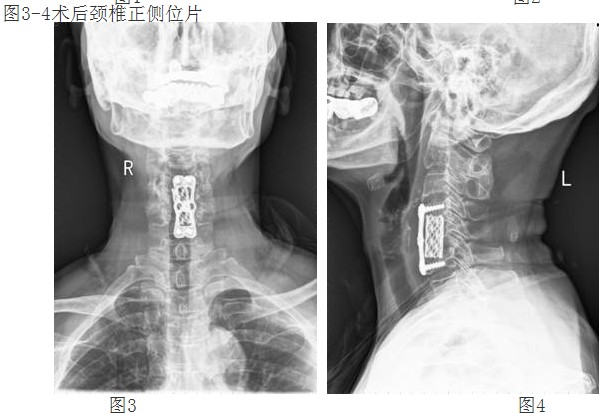

經(jīng)過譚主任和全科醫(yī)護(hù)人員充分的術(shù)前準(zhǔn)備和討論,對患者實(shí)施了頸椎前路頸4/5、頸5/6椎間盤摘除、頸5椎體次全切除、椎管減壓鈦網(wǎng)植骨融合、頸前路鈦板固定術(shù)。手術(shù)取得了成功。術(shù)后第二天,李阿婆的四肢麻木就明顯減輕,握手能力和手臂力量都明顯好轉(zhuǎn)。

經(jīng)頸前路減壓植骨融合內(nèi)固定術(shù)屬復(fù)雜高難度高風(fēng)險手術(shù),該技術(shù)的成功開展,填補(bǔ)了我院在該領(lǐng)域的空白,表明我院脊柱外科技術(shù)邁上了更高的臺階。(后附典型病例照片)